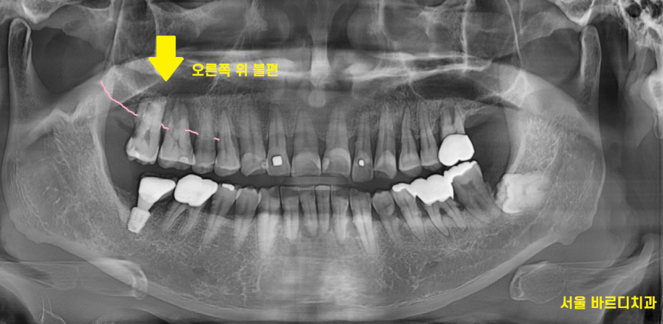

불편을 호소하신 오른쪽 치아

x-ray 상에서 잇몸뼈가 많이 내려가

치아를 흔들어보았습니다.

정상적인 치아는 잇몸뼈가 꽉 잡아주어

흔들리지 않아야합니다.

환자분은

어금니가 들썩 들썩

위 아래, 좌우로 움직였습니다.

치아가 뽑힐정도로 말이죠.

230414

잇몸뼈가 남아 있지 않다는 뜻입니다.